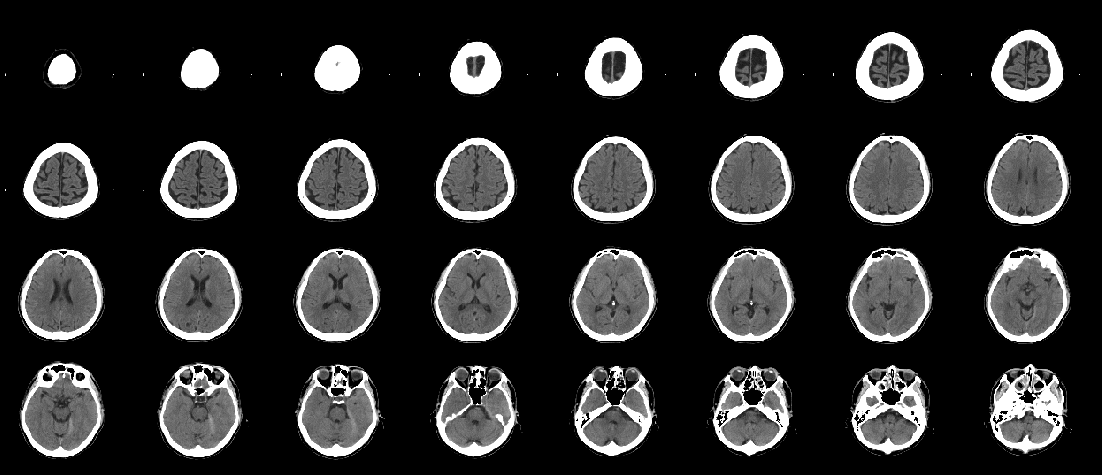

Figure 12: BCT most likely to have an abnormality according to the logarithm posterior probability out of the 33 abnormal BCTs used for testing. This is an enlarged version of a part of Fig. 11, and the lesion is pointed out with red arrows.

Refer to caption

Figure 13: BCT second most likely to have an abnormality according to the logarithm posterior probability out of the 33 abnormal BCTs used for testing (acute infarction in the left posterior cerebral artery territory).

Figure 14: BCT second most likely to have an abnormality according to the logarithm posterior probability out of the 33 abnormal BCTs used for testing. This is an enlarged version of a part of Fig. 13, and the lesion is pointed out with red arrows.

Figures 11 and 12 show the BCT most likely to have an abnormality according to the logarithm posterior probability out of the 33 abnormal BCTs used for testing. Figures 13 and 14 show the BCT second most likely to have an abnormality according to the logarithm posterior probability out of the 33 abnormal BCTs used for testing.